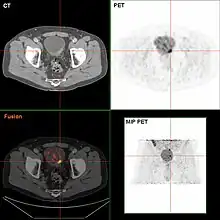

Diagnosis

Bladder tumor in FDG PET due to the high physiological FDG-concentration in the bladder, furosemide was supplied together with 200 MBq FDG. The uptake cranial to the lesion is a physiological uptake in the colon.

If invasive or high grade (includes carcinoma in situ) cancer is detected on TURBT, an MRI and/or CT scan of the abdomen and pelvis or urogram and CT chest or x-ray chest should be conducted for disease staging and to look for cancer spread (metastasis). Increase in alkaline phosphatase levels without evidence of liver disease should be evaluated for bone metastasis by a bone scan.[1] Although 18F-fluorodeoxyglucose (FDG)-positron emission tomography (PET)/CT has been explored as a viable method for staging, there is no consensus to support its role in routine clinical evaluations.[54]